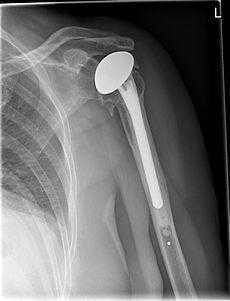

Полная замена плечевого сустава

Полная замена плечевого сустава или тотальное эндопротезирование плечевого сустава. Плечевой компонент зафиксирован внутри плечевой кости. Гленоидный компонент замещает суставную впадину. © Wikipedia

При полной замене плечевого сустава заменяются оба компонента сустава: плечевая головка и суставная впадина. Это самый распространенный метод замены плечевого сустава. При износе обеих поверхностей сустава, как плечевой головки так и суставной впадины, необходим полный эндопротез. При таком методе замены удаляется сегмент плечевой головки, наиболее близкий к суставу. Затем внутренняя часть (пространство костного мозга) плечевой кости подготавливается для внедрения ножки протеза.

Ножка протеза имплантируется вовнутрь кости. Одним из наиболее тяжелых осложнений при полной замене плечевого сустава является ослабление гленоидного компонента. Это ведет к возникновению боли и ограничению подвижности.

Поэтому тщательная диагностика, оптимальный подбор размера и подгонка компонентов протеза является необходимым аспектом плечевой хирургии. Специалисты по плечевым суставам должны также детально оценить риск таких осложнений, как остеопороз (снижение плотности кости).